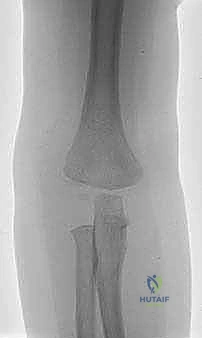

يُعرف كسر اللقيمة الوحشية للعضد بأنه انفصال أو تهشم يصيب الجزء الخارجي (الوحشي) من النهاية السفلية لعظم العضد (العظم العلوي للذراع) بالقرب من مفصل الكوع. هذه الكسور ليست نادرة على الإطلاق؛ فهي تمثل ما بين 10% إلى 20% من إجمالي كسور الكوع عند الأطفال، وتأتي في المرتبة الثانية مباشرة بعد كسور فوق اللقمتين (Supracondylar fractures). تكمن خطورة هذا الكسر في أنه يمتد عادة ليخترق سطح المفصل نفسه، والأخطر من ذلك أنه يمر عبر "صفيحة النمو" (Growth Plate) وهي المنطقة الغضروفية الحساسة المسؤولة عن نمو العظم وتطوره الطبيعي.

لماذا الكسر مخادع؟ في الأطفال الصغار، تكون أجزاء كبيرة من مفصل الكوع عبارة عن غضاريف لم تتحول إلى عظم صلب بعد (لم تتعظم). الأشعة السينية لا تظهر الغضاريف، بل تظهر العظام فقط. لذلك، قد يبدو الكسر في الأشعة صغيراً جداً (مجرد قشرة عظمية صغيرة مكسورة)، بينما في الواقع، هناك كتلة غضروفية كبيرة جداً (تحتوي على سطح المفصل وصفيحة النمو) قد انفصلت تماماً وتدور حول نفسها.

هنا تتجلى خبرة الجراح. الطبيب غير المتخصص قد يرى الأشعة ويقول للآباء "إنه كسر بسيط يحتاج لجبس"، بينما الخبير مثل أ.د. محمد هطيف يدرك من خلال النظرية التشريحية وخبرته الطويلة أن هذا الكسر غير مستقر ويحتاج لتدخل جراحي.

* الدرجة الأولى (Stage 1): الكسر غير متحرك من مكانه (أقل من 2 ملم)، والمفصل سليم.

* الدرجة الثانية (Stage 2): الكسر متحرك (أكثر من 2 ملم) ولكن الجزء المكسور لم يدر حول نفسه.

* الدرجة الثالثة (Stage 3): الكسر متحرك بالكامل، والقطعة المكسورة دارت حول نفسها بسبب شد العضلات، مما أدى لانخلاع جزئي في المفصل.